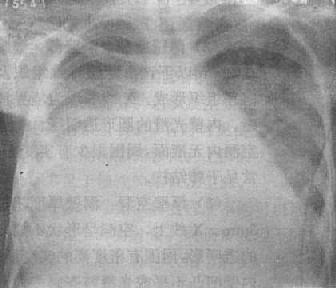

图3-1-31 肺泡癌

两肺出现大小不等多发小结节影,右中下肺野病灶融合成一片致密影,肋膈角及膈均不见,指明有胸腔积液

(3)细支气管肺泡癌:早期可表现为孤立的结节状或肺炎样浸润影,其中可见含气的支气管或小的透明区,透明区系由于部分肺泡尚含有空气所致。晚期可表现为弥漫性病变,在一肺或两肺出现大小不等、境界不清的结节状或斑片状影,为腺泡结节状占位病变(图3-1-31)。进一步发展,这些病灶可以融合成大片絮状影,形成癌性实变。